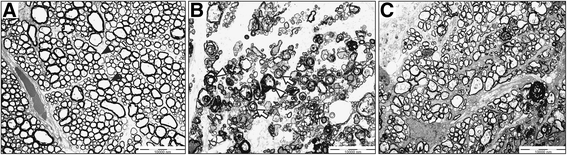

缺血被认为是各种眼部疾病的主要致病性疾病,例如糖尿病性视网膜病,视网膜动脉/静脉闭塞和青光眼...